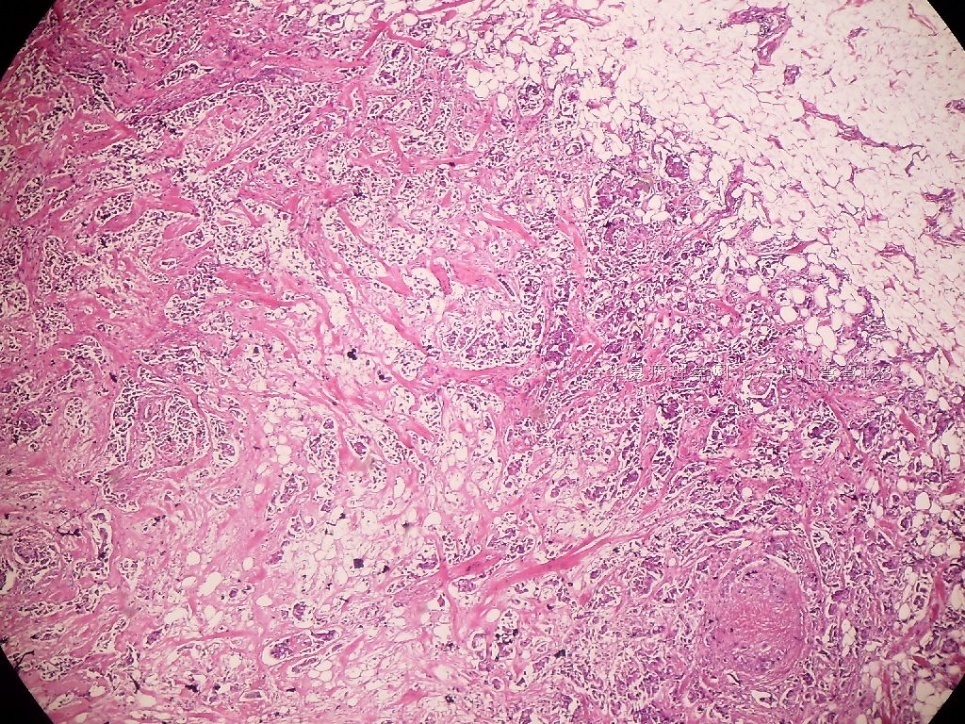

姓    名: ××× 性别:  女 年龄:  45

标本名称:  左侧近乳晕处肿物

简要病史:  患者描述有疼痛

肉眼检查:  肿物一个2.5*2*1厘米,切面灰白质地硬。

• 浸润性导管癌?图1

上皮样细胞,大部分粘附成团成巢,明显浸润。大部分细胞大,核级别高,少数图中见松散的小细胞。未见原位癌。

大细胞考虑浸润性导管癌(3级),小细胞要排除小叶癌。如果有条件请做免疫组化。

Most likely it is INVASIVE DUCTAL CARCINOMA.

DO ER/PR/HER2 STAINS

应该是浸润性导管癌,标本可能有部分自溶现象。